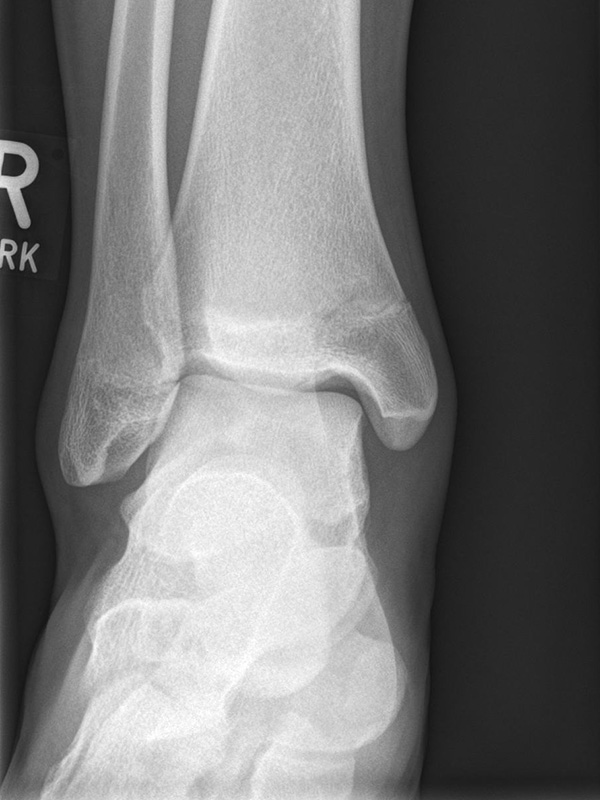

Sprunggelenk anterior-posterior (ap) ohne Belastung

Kennzeichen des Röntgenbildes:

• Der Talus ist leicht außenrotiert.

• Der talofibulare Gelenkspalt wird partiell durch die distale Fibula überdeckt.

• Das anteriore Tuberkel der Tibia überlappt die distale Fibula.

Besondere Bemerkungen zum Beispielbild:

• Innenknöchelfraktur bei einem Jugendlichen.

• Keine relevante Dislokation.

• Die Wachstumsfugen sind noch erkennbar, im Wesentlichen aber geschlossen.